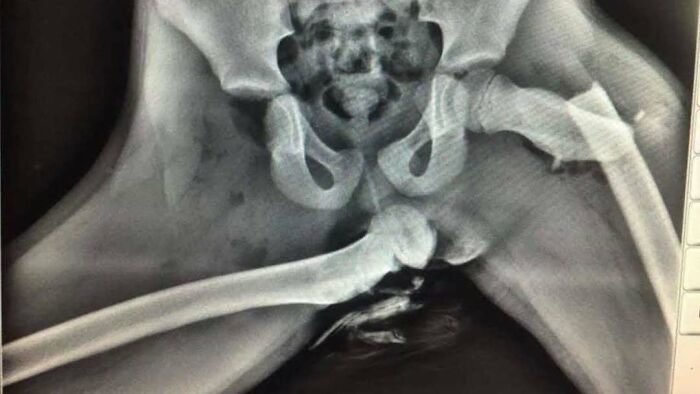

Por qué nunca debes apoyar los pies en el salpicadero de un coche. Una mujer sufrió lesiones terribles tras apoyar los pies en el salpicadero de un coche. Esto le provocó una fractura de cadera.